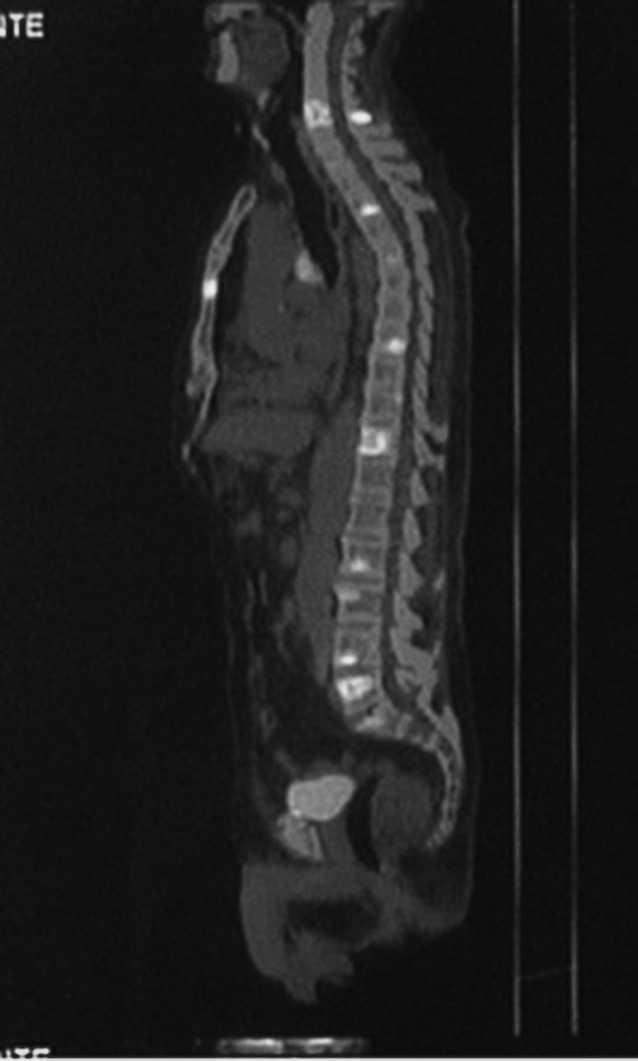

Un varón de 76 años acudió al hospital por fiebre y disfonía. Quince años antes había sido intervenido quirúrgicamente, tras sufrir la rotura de un aneurisma de la aorta abdominal, realizándose una endoaneurismorrafia y un injerto aorto-bifemoral. Dos meses antes había ingresado por presentar una miositis abscesificada en muslo derecho que precisó drenaje quirúrgico. La exploración era anodina a excepción de las secuelas de las intervenciones quirúrgicas previas y la disfonía. Entre los datos analíticos destacaba la existencia de leucocitosis (11.600/ml) con neutrofilia, anemia (Hb: 10 g/dl) normocítica normocrómica, elevación de la velocidad de sedimentación globular (VSG) (60 mm/ primera hora) y aumento de la lacticodeshidrogenasa (LDH) (604 UI/l). El urinocultivo fue negativo, mientras que en los hemocultivos creció una Escherichia coli. En el examen otorrinolaringológico se observó la existencia de una parálisis de la cuerda vocal derecha. La radiografía de tórax mostraba signos de hipertensión arterial pulmonar y atrapamiento aéreo. La tomografía computarizada (TC) de cuello y tórax puso de manifiesto la existencia de un nódulo de 1,3 cm de diámetro en lóbulo superior derecho (LSD), que hacía contacto con la pleura de la pared torácica posterior. En la gammagrafía ósea con 99mTc se observaron varios focos hipercaptadores en parrilla costal izquierda y esternón, así como un patrón heterogéneo irregular en la columna vertebral. La tomografía por emisión de positrones (PET/ TC) reveló la existencia de captación sugestiva de malignidad en el nódulo pulmonar del LSD (fig. 1), en los ganglios mediastínicos, glándula suprarrenal izquierda y parénquima hepático, así como múltiples focos hipercaptantes en el esqueleto compatibles con una diseminación ósea metastásica (figs. 2, 3 y 4). En las citologías de esputo y en el aspirado bronquial se observaron células atípicas sugestivas de carcinoma no microcítico (carcinoma indiferenciado).

Fig. 3. Tomografía por emisión de positrones con fluorodesoxiglucosa (PET-FDG) (A) y PET/tomografía computarizada (TC) (B), corte sagital, en las que se observan múltiples imágenes de hipercaptación en el esqueleto compatibles con una diseminación ósea metastásica.